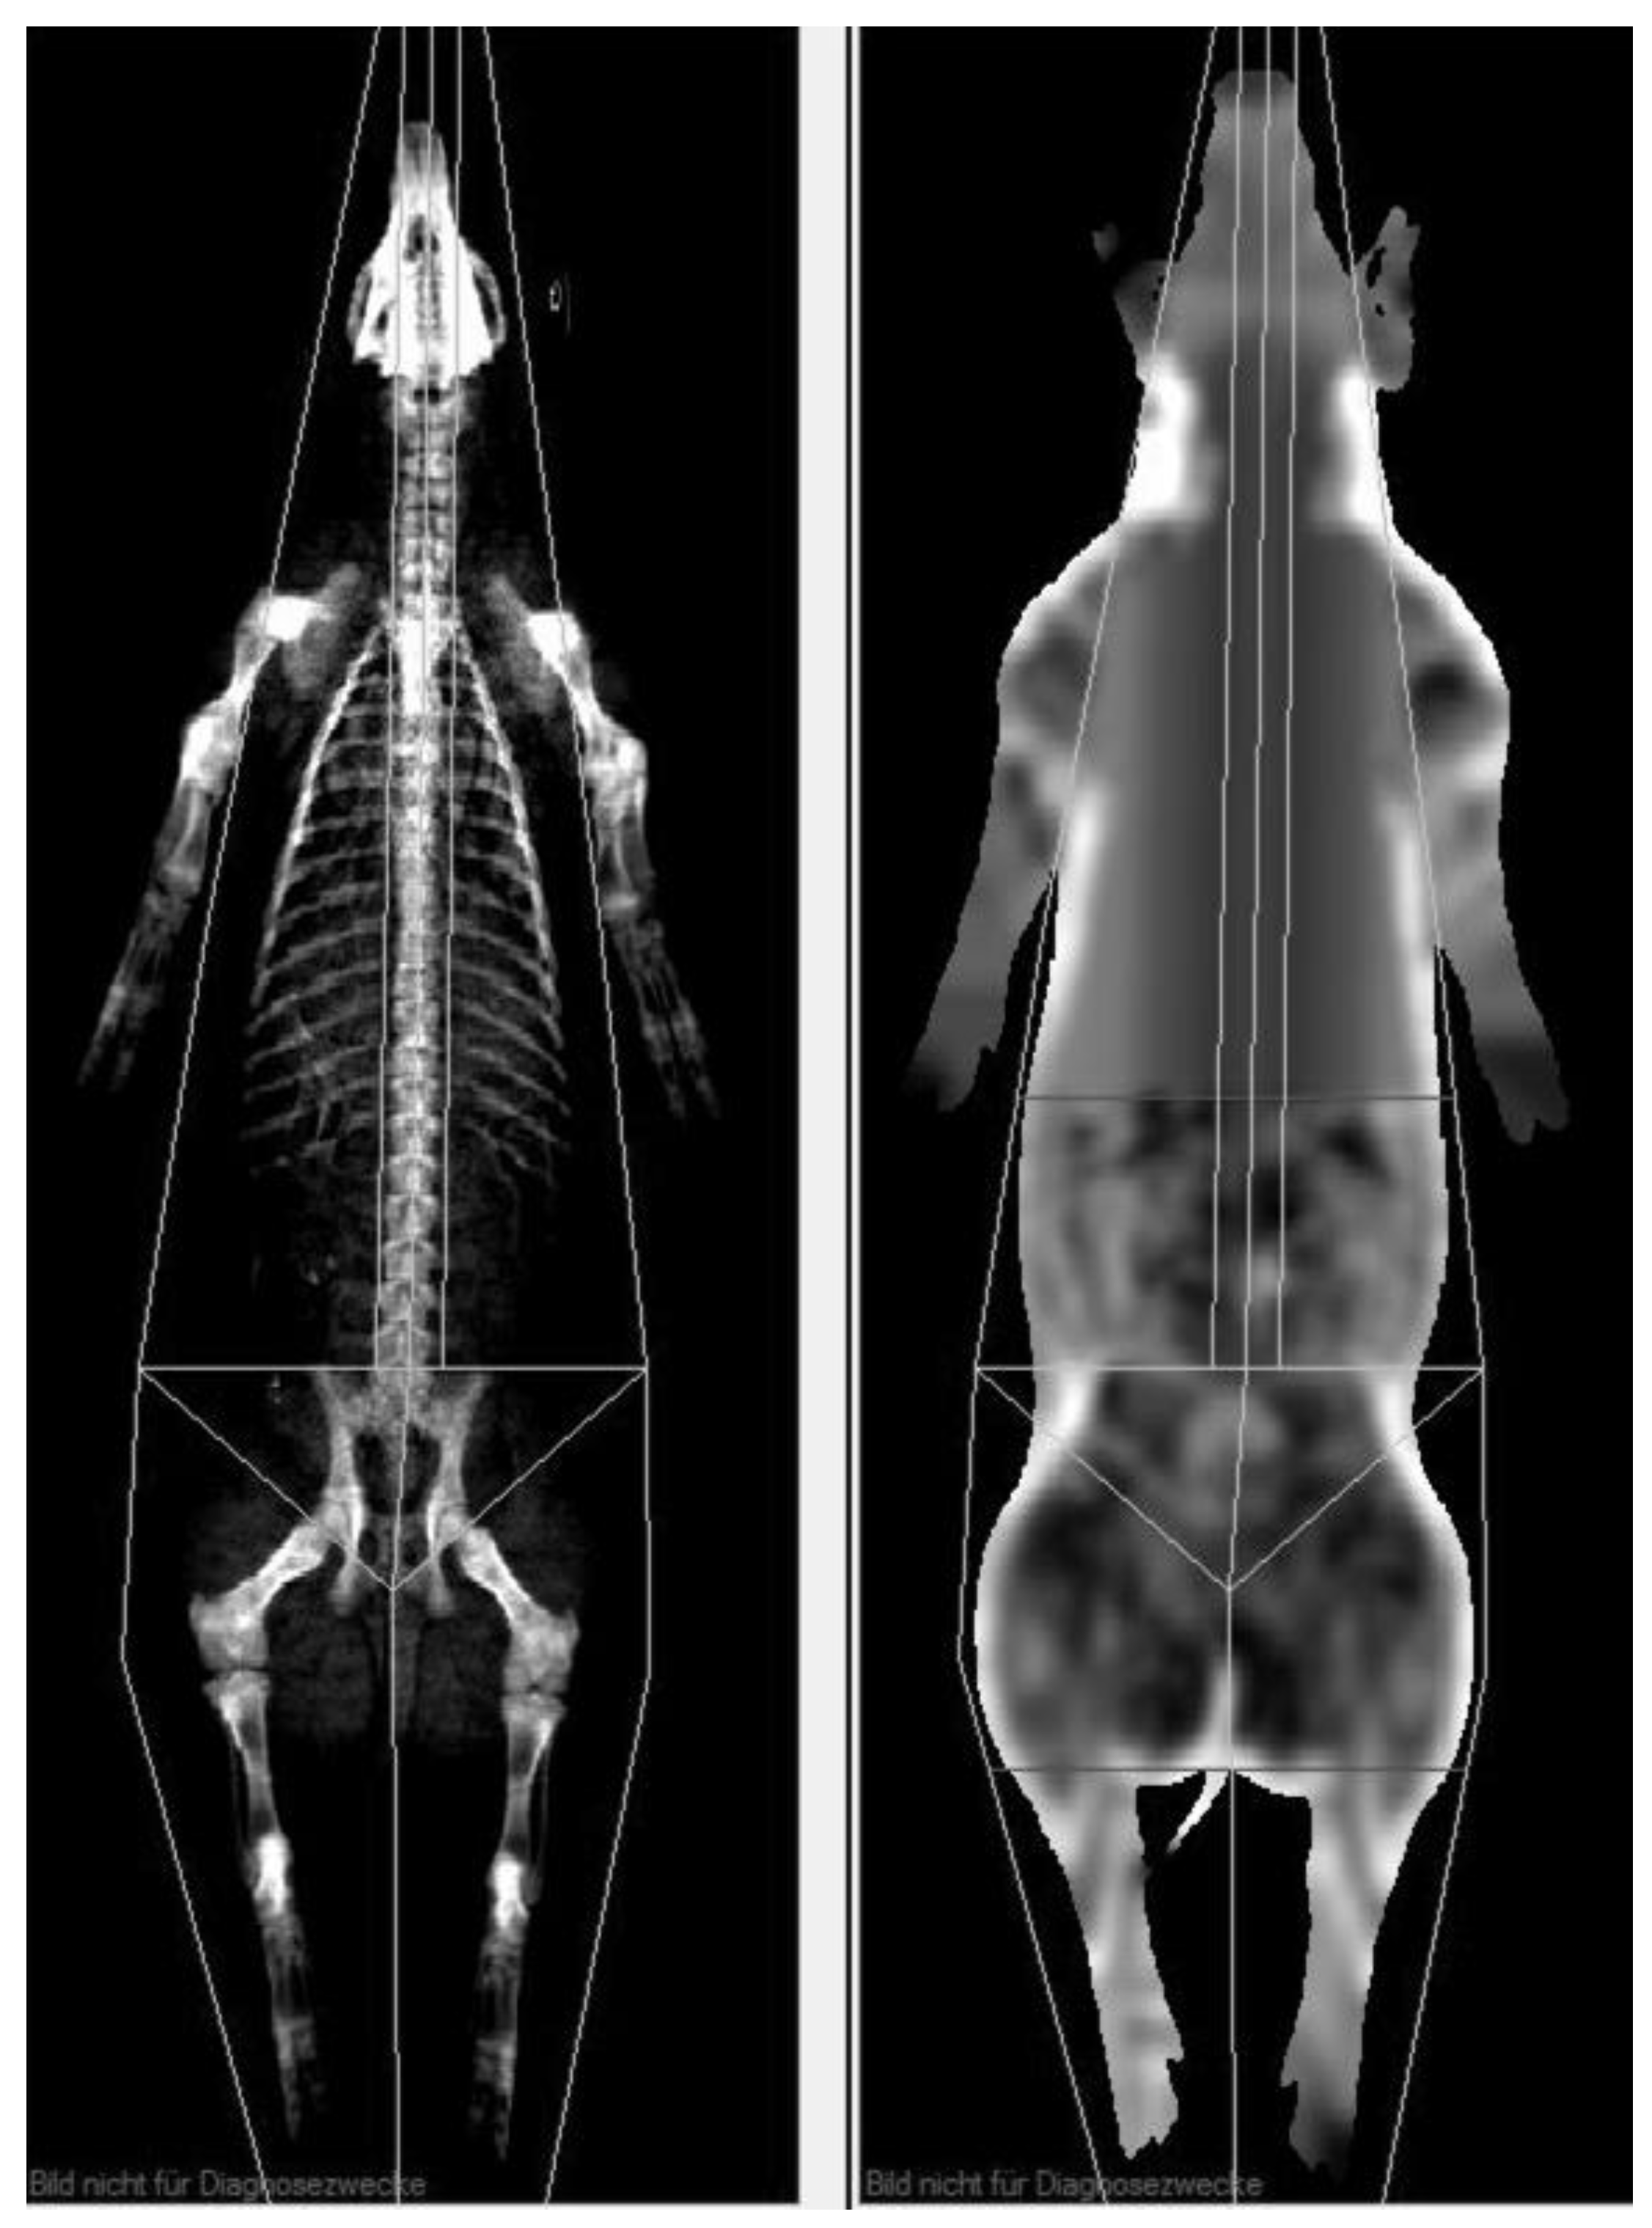

2.2.2. Dual Energy X-ray Absorptiometry

2.3.2. DXA Evaluation